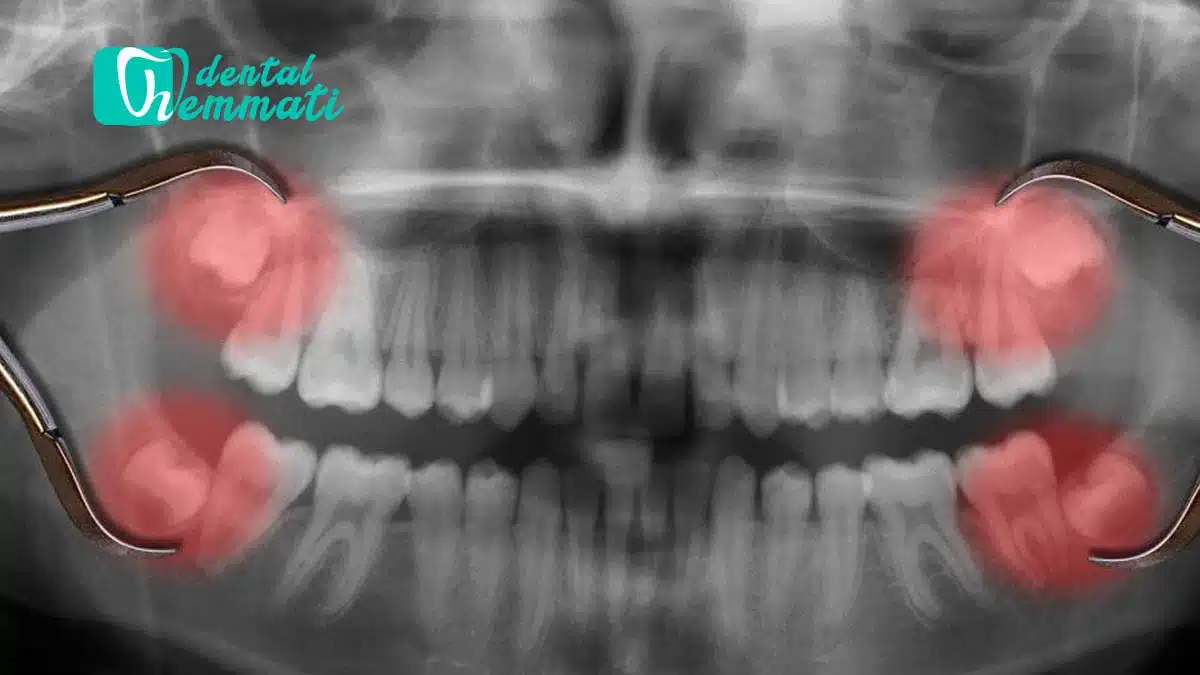

۲. رشد ناقص یا نهفتگی دندان

زمانی که دندان عقل نتواند به طور کامل از لثه بیرون بیاید، به آن دندان نهفته گفته میشود. دندانهای نهفته معمولاً باعث التهاب و تورم لثه میشوند و میتوانند منبع درد مزمن یا گاهبهگاه باشند.

۱. دندان عقل نهفته یا نیمه نهفته

اگر دندانهای عقل بهصورت نهفته یا نیمهنهفته باشد و ایجاد درد، التهاب یا عفونت کند، کشیدن آن بهترین گزینه است.